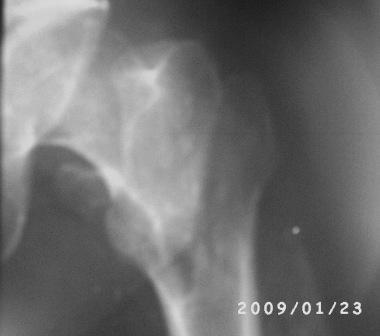

Вертельный перелом уже срастается в приемлемом положении отломков. Для сохранения шеечно-диафизарного угла в проксимальной опоре аппарата по оси шейки можно ввести 2-3 стержня.

Лучше сделать остеоклазию на уровне диафиза секциями аппарата (ротацией), затем проводить дистракцию темпом 2-4 мм/сут дробно, в пределах переносимости пациентом. После восстановления длины и сопоставления диафиза по оси закрыто заштифтовать. Имеющийся стержень вполне подойдет, поскольку вертельный перелом уже не будет требовать остеосинтеза.